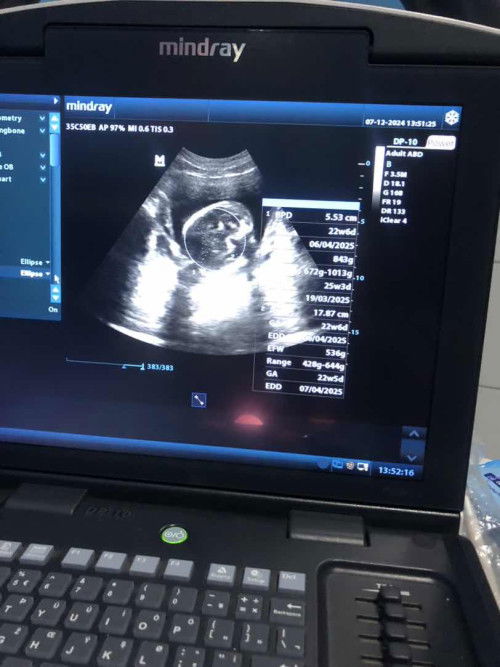

Bund mau sharing pengalaman aku pas kmrin uk 5 bulan lebih pas diperiksa diliat di usg bayiknya malah masuk panggul dan nunggngin jadi ga keliatan kn bund bb bayi ku waktu itu 500gram itu krna bayinya kecil apa gmna yaa bund soalnya takut slrg juga kerasa gerakannya dibawah trs bund#bantujawab #ingintahu #firstmom